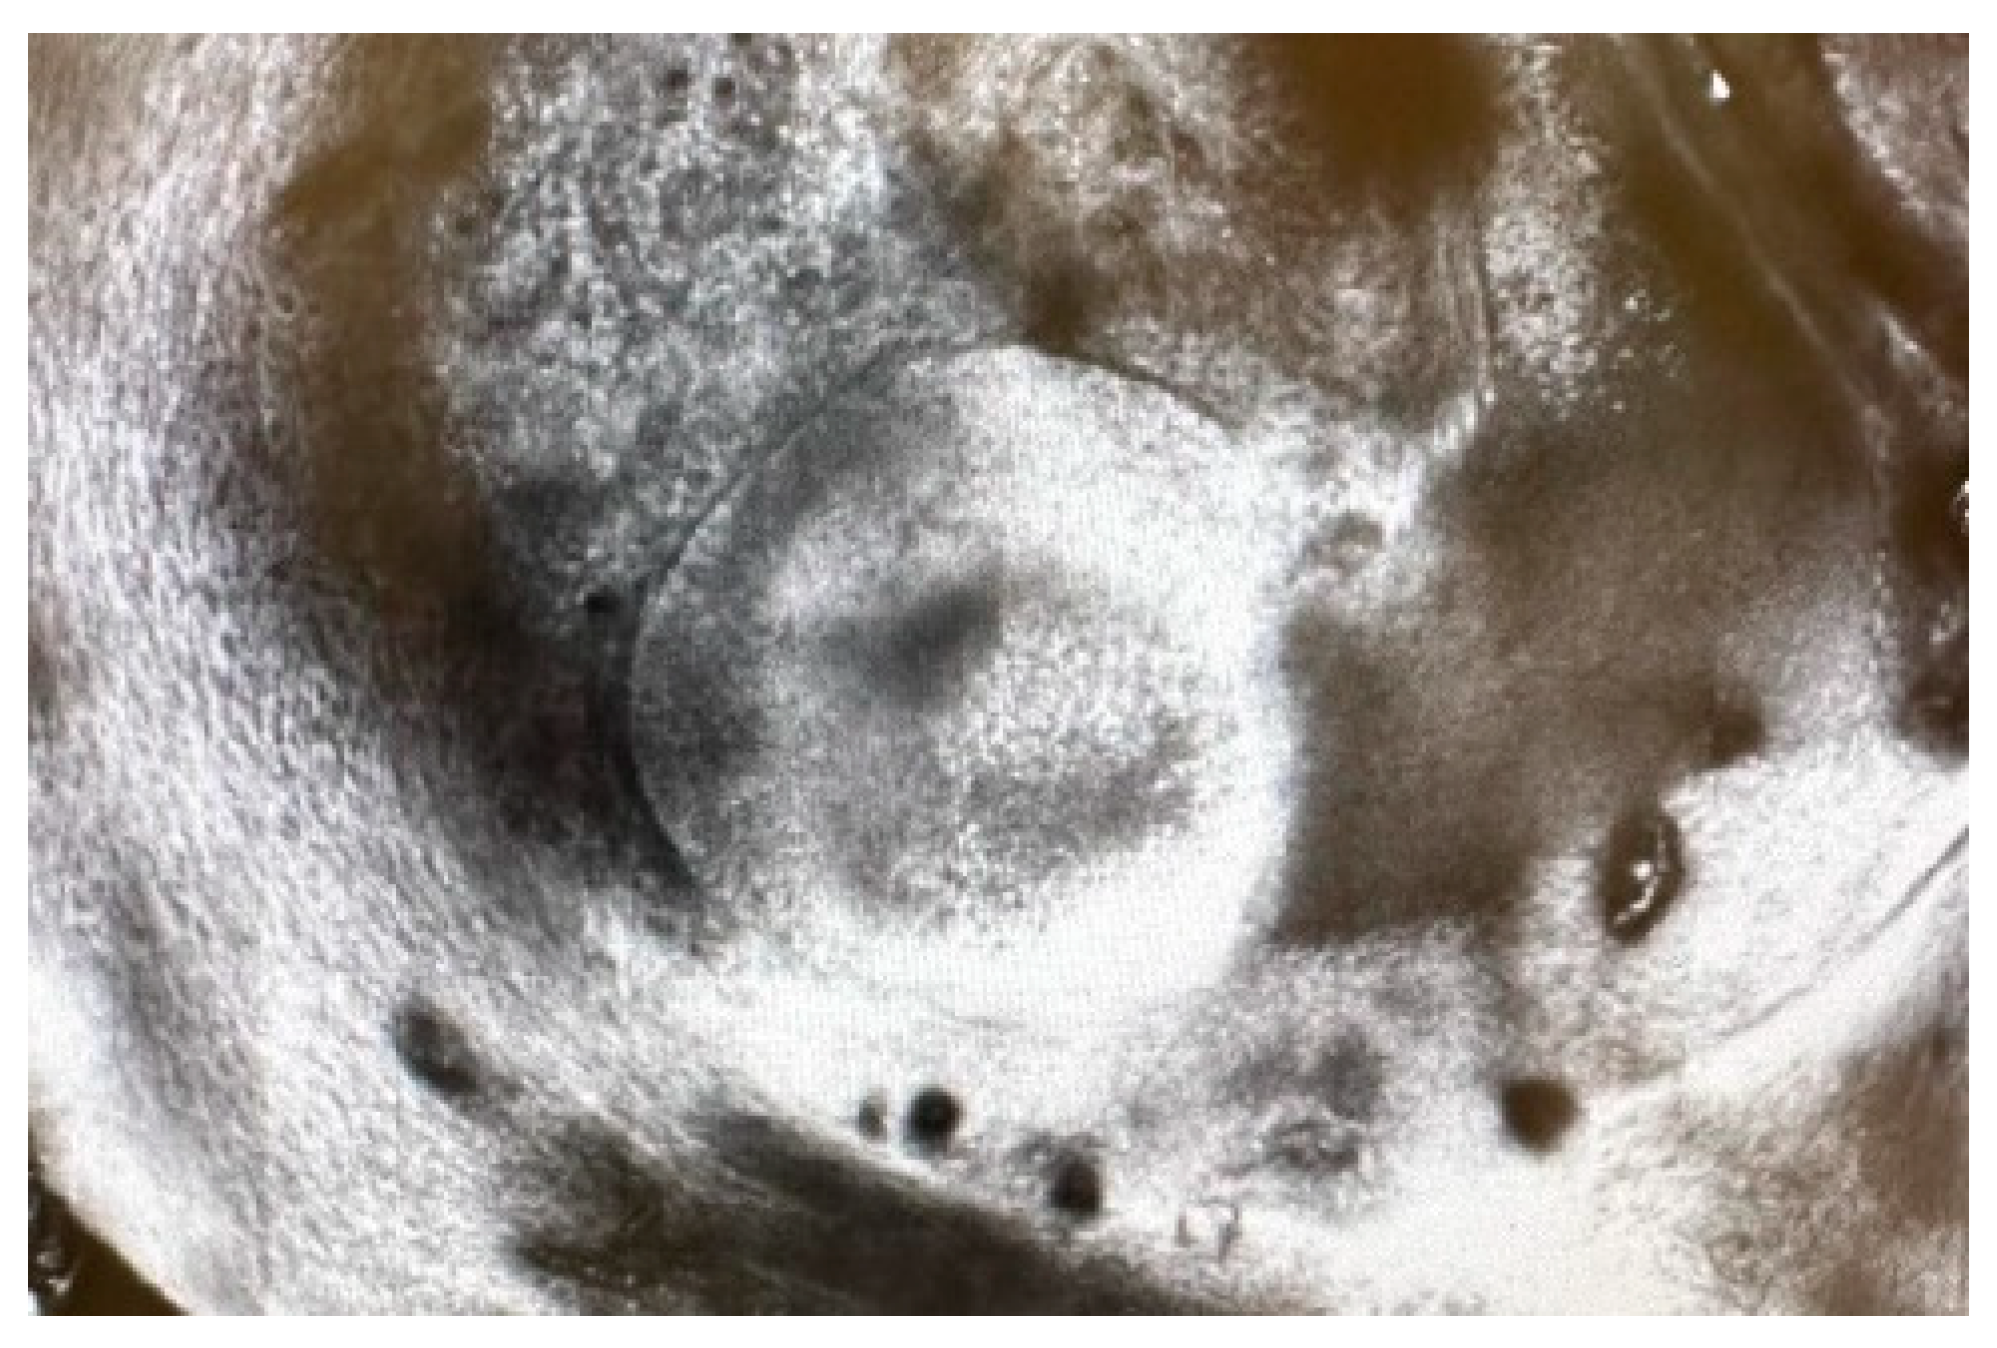

A dermoscopy of the lesions was performed revealing ovoid yellowish structures (Figure 2) that correspond to granulomas identified on confocal microscopy (Figure 3). We did not find any data reported in the literature about dermoscopy or confocal microscopy features seen in actinomycosis.

Figure 3. Confocal microscopy image showing granulomas.